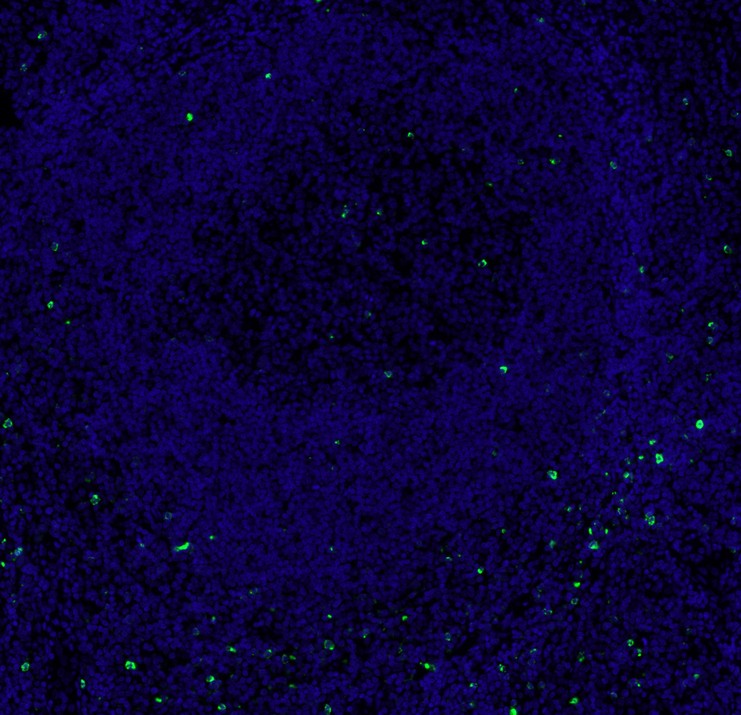

mIHC analysis of human tonsils tissue (Formalin/PFA-fixed paraffin-embedded sections) with Rabbit anti-LAG-3 antibody (HA721358) at 1/400 dilution. The immunostaining was performed with the IRISKitCmTSA Kit (900808). Heat mediated antigen retrieval with Tris-EDTA buffer (pH 9.0) for 30 mins at 95℃. DAPI (blue) was used as a nuclear counter stain. Image acquisition was performed with Olympus VS200 Slide Scanner.